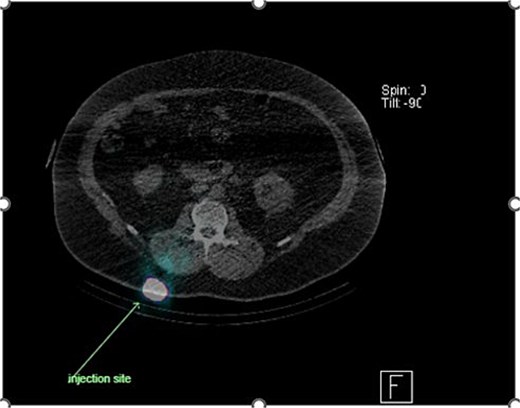

Preoperative lymphoscintigraphy was performed to detect the sentinel lymph node (Fig. 1), expecting it to be in the right inguinal region (Fig. 2). However, drainage to both the right axillary (Fig. 3) and inguinal areas was demonstrated. During surgery, a gamma camera confirmed drainage to both regions (Fig. 4). Blue dye was injected around the previous scar, and sentinel nodes were dissected guided by both blue dye and gamma camera for histopathology.

Unexpected drainage visualized toward the right axillary lymph nodes.